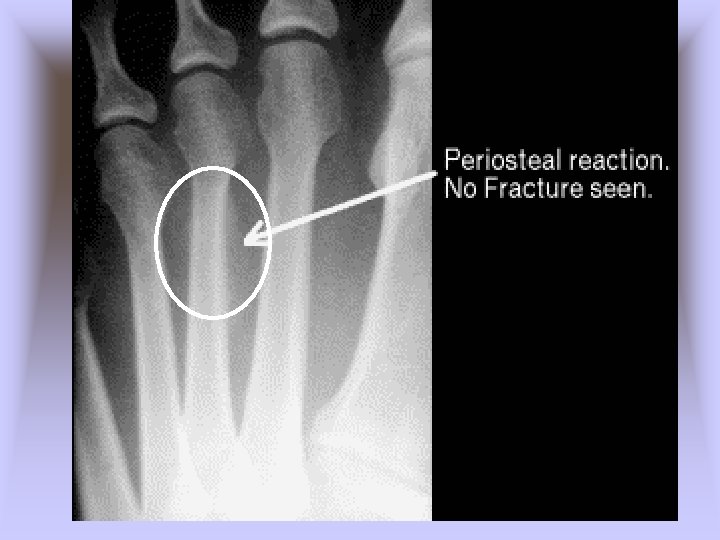

• Metatarsal Stress Fractures – Cause of Injury • 2 nd metatarsal fracture (March fracture) • Change in running pattern, mileage, hills, or hard surfaces • Often the result of structural deformities of the foot or training errors (terrain, footwear, surfaces) • Often associated with Morton’s toe – Signs of Injury • Pain and tenderness along second metatarsal • Pain with running and walking • Continued pain/aching when non-weight bearing

– Care • Determine cause of injury • Generally good success with modified rest and training modifications (pool running, stationary bike) for 2 -4 weeks • Return to running should be gradual over a 2 -3 week period with appropriate shoes